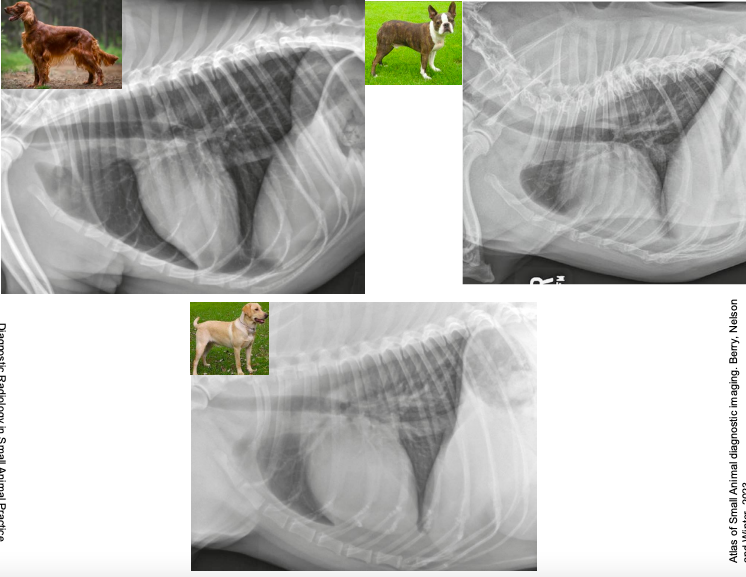

En perro mas achatada, gato mas alargado. musculo del psoas en gato obscura parte del diafrgama.

Importante saber ver las partes del corazón y donde se encuentra (En laterolateral mas facil, derechoizquierda)

- En perro está entre el 3er y 7o espacio intercostal

- En gato está entre la 4a y 7a costilla